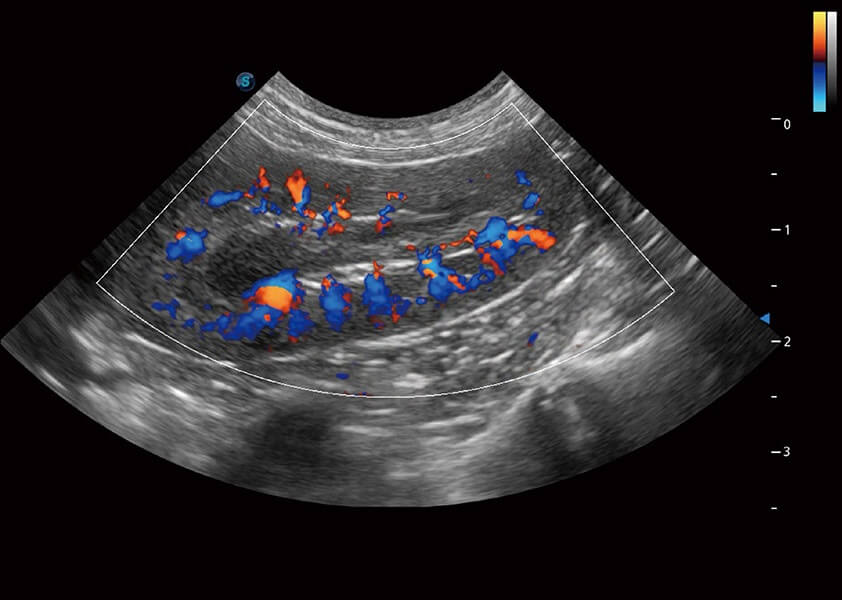

ProPet 60 作为一款高端台式动物超声设备,为动物医生的日常诊断提供了一系列贴合动物临床需求、解决临床实际问题的高级成像功能。凭借全系列高清探头,满足医生对腹部、心脏、生殖、浅表、肌骨等成像的所有需求,切实帮助您提升检查效率,提高诊断信心。

动物是人类最亲密的朋友和最值得信赖的伙伴。米兰官方网站也一直致力于探索动物专用的超声影像解决方案。 全新推出的ProPet系列,是米兰官方网站在动物超声影像智能化、专业化、精准化的一次跨越式革新。动物不能用言语来表述自己的不适,通过超声影像,ProPet系列搭建了动物医生与不同物种沟通的“桥梁”,为动物医生注入了“治愈之力”。